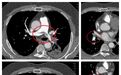

为明确诊断,医生迅速为小李安排下肢血管彩超检查,结果证实了担忧:右侧小腿肌肉内静脉附壁血栓,右下肢深静脉血栓形成,且血栓头端部分游离,随时可能脱落引发致命性肺栓塞。进一步的血气分析显示,小李存在严重低氧血症,强化肺动脉 CTA 更提示双肺已出现大量血栓,救治刻不容缓!

△强化肺动脉 CTA 提示双肺已出现大量血栓